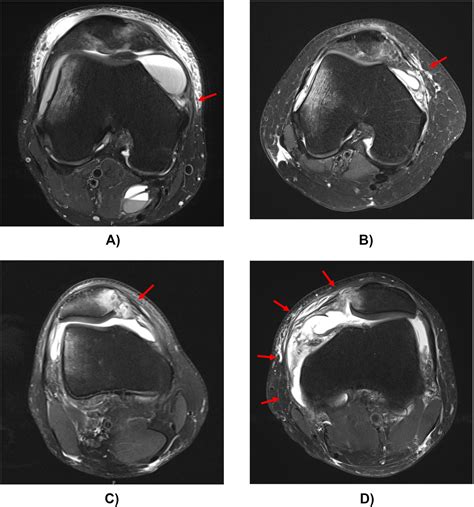

• Imaging Studies: X-rays, MRI, and CT scans can provide detailed images of the knee joint, helping to identify any structural abnormalities, fractures, or soft tissue injuries. MRI is particularly useful for visualizing the MPFL and other ligaments.

• medial patellofemoral ligament mri